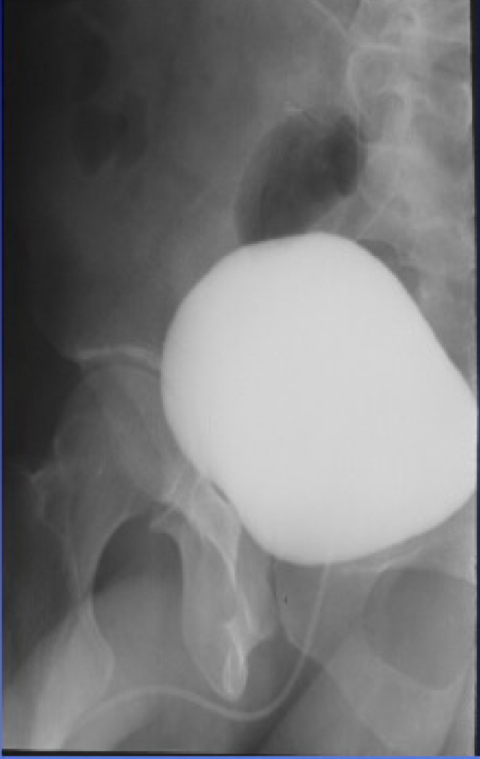

New cards

What is this X-ray demonstrating?

AP cystogram